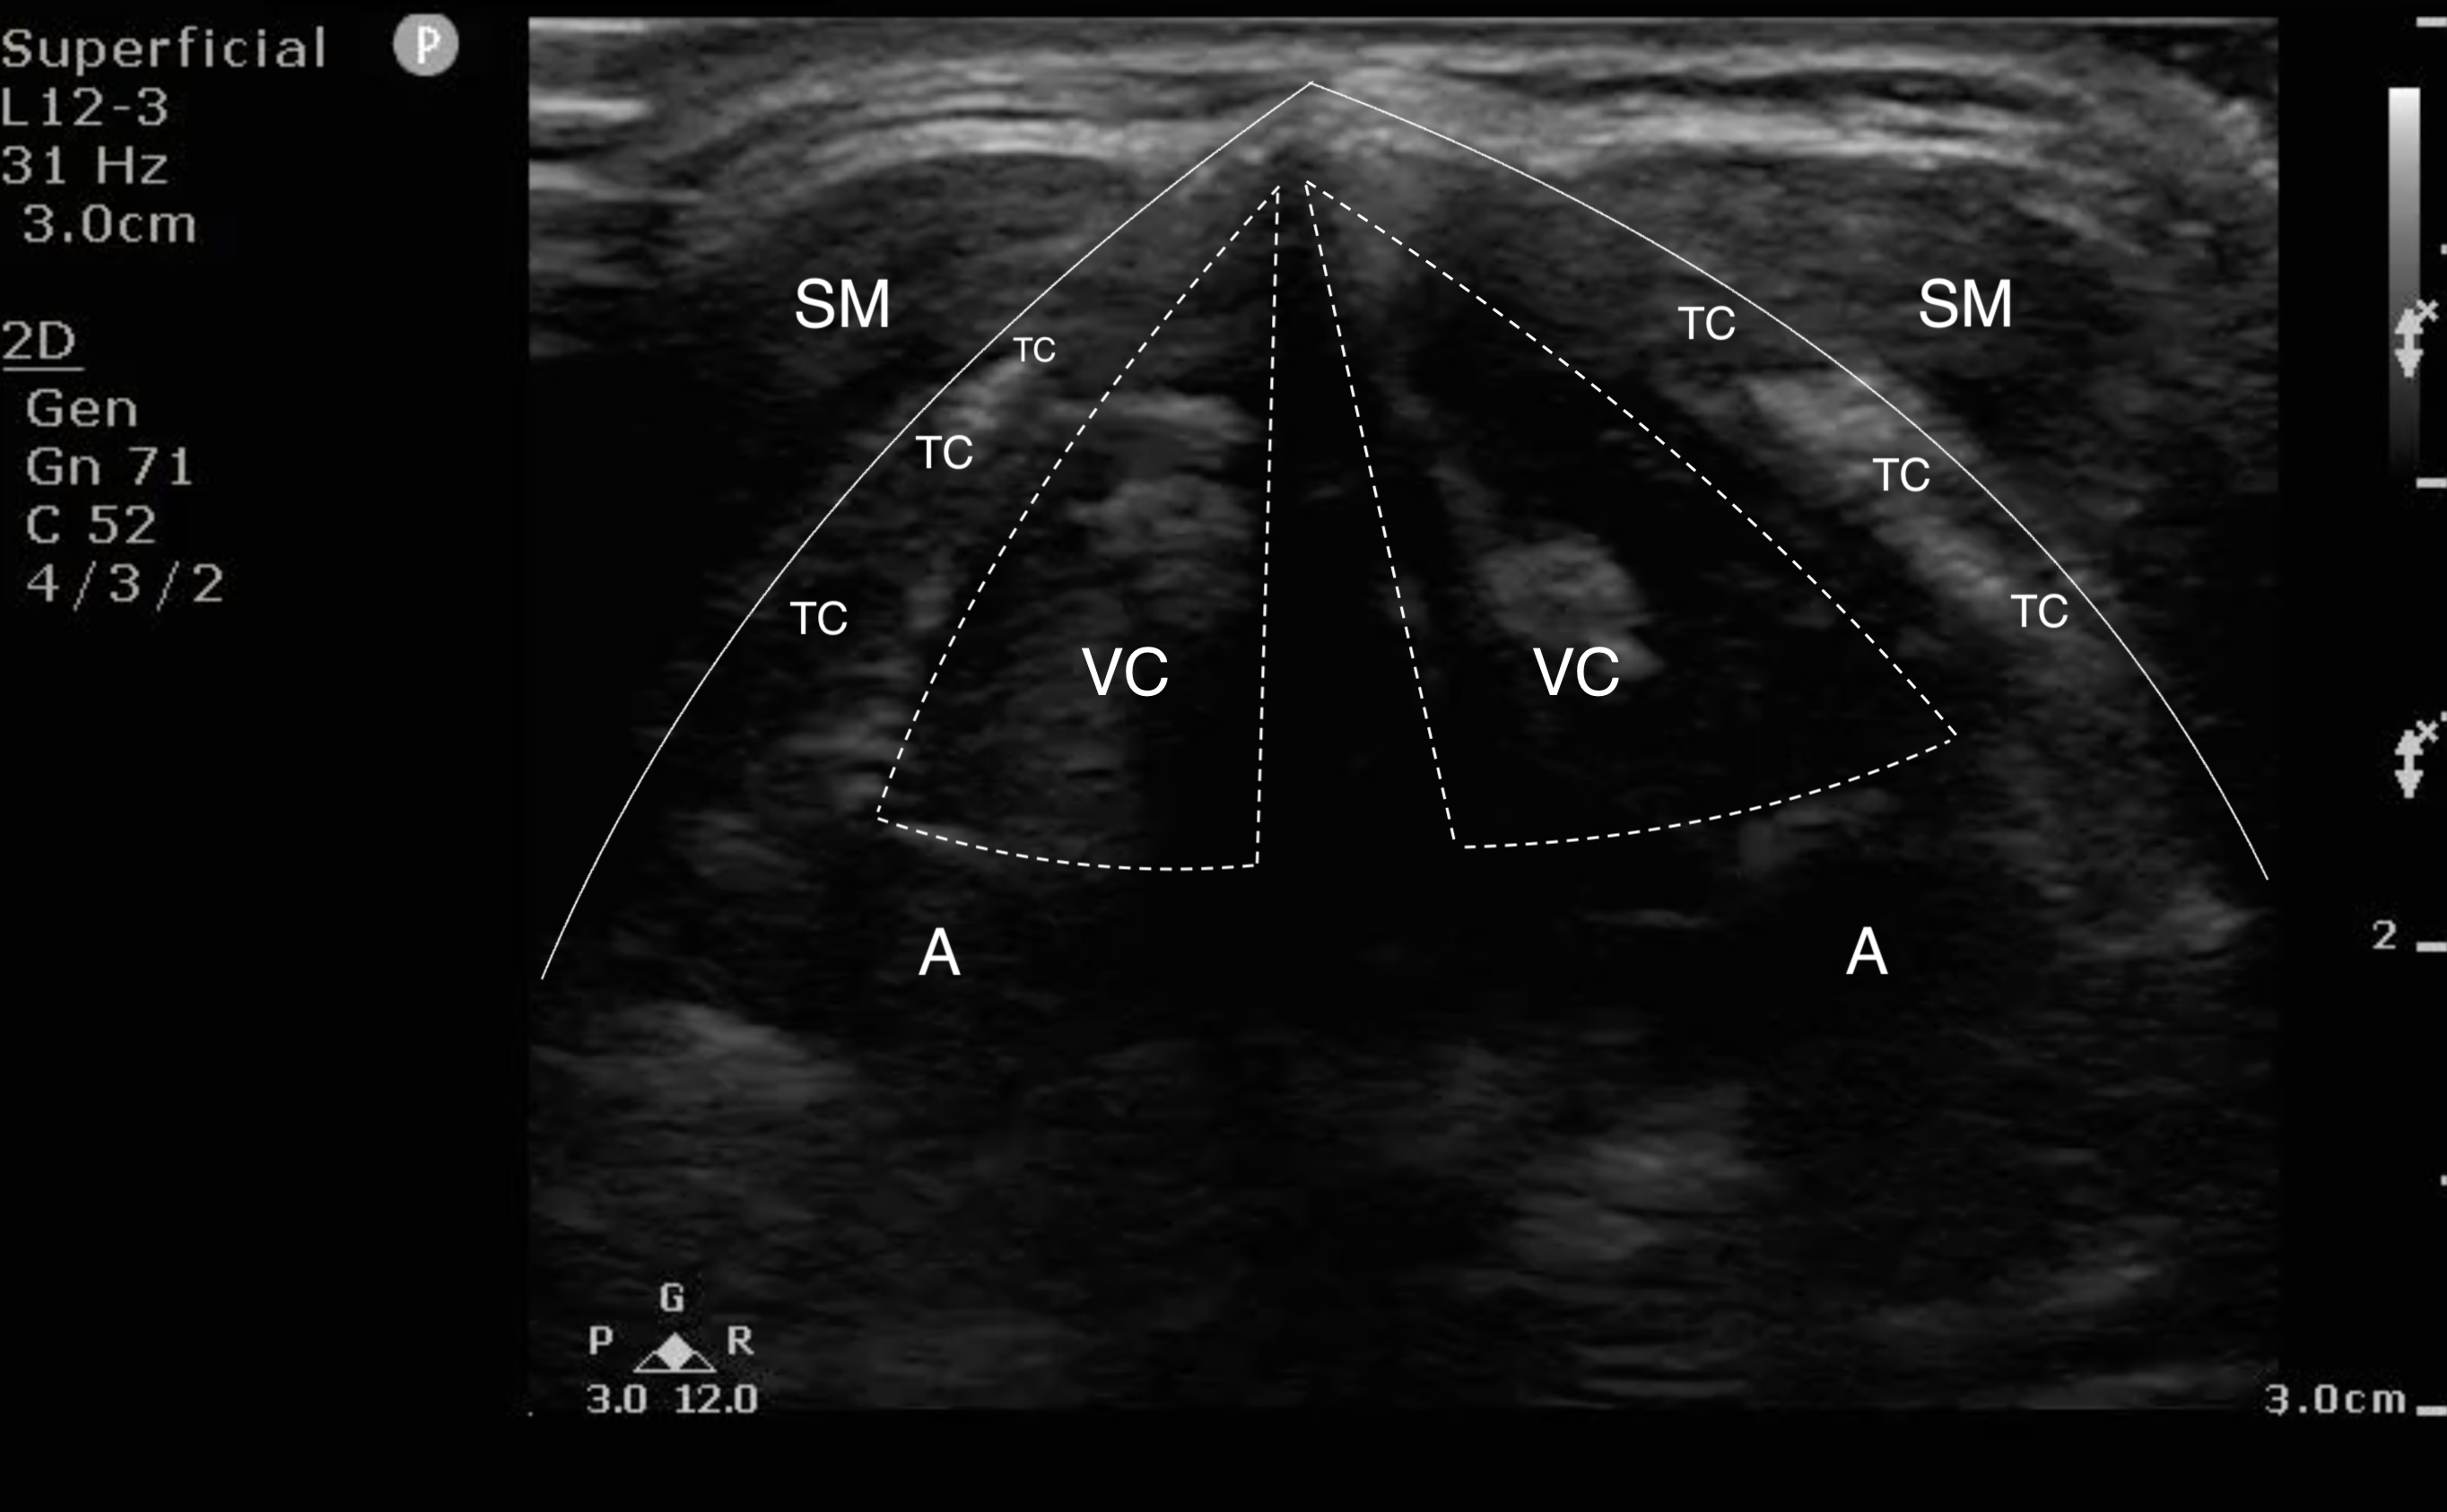

- Figure 4a and b. Step 4: In males, the thyroid cartilage is prominent, serving as a good landmark. Even in women, the thyroid cartilage is difficult to miss. It is an upside-down V shaped structure. Superficial to the thyroid cartilage are the hypoechoic strap muscles (SM), and deep to the thyroid cartilage (TC) are the vocal cords (VC). Deep to the vocal cords, you see the arytenoids (A).